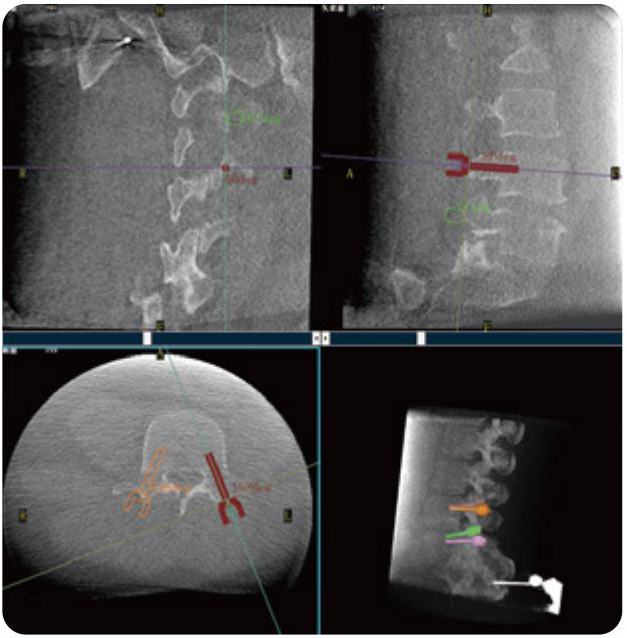

PL300B可應(yīng)用于多節(jié)段脊柱外科手術(shù),輔助醫(yī)生定位病灶部位,為脊柱外科手術(shù)(經(jīng)皮椎體成形術(shù)、椎弓根螺釘內(nèi)固定術(shù)等術(shù)式)提供術(shù)前手術(shù)流程規(guī)劃、入釘位置、角度可視化引導(dǎo),模擬仿真入釘輔助。

PL300B搭配普愛醫(yī)療自主研發(fā)生產(chǎn)的平板3D C形臂,借助一體化自適應(yīng)配準(zhǔn)( 軌跡配準(zhǔn))技術(shù),通過(guò)追蹤C(jī)形臂三維采集軌跡,自動(dòng)完成圖像坐標(biāo)建立和系統(tǒng)坐標(biāo)配準(zhǔn)。配準(zhǔn)精度更高,操作步驟少,系統(tǒng)運(yùn)作效率高。